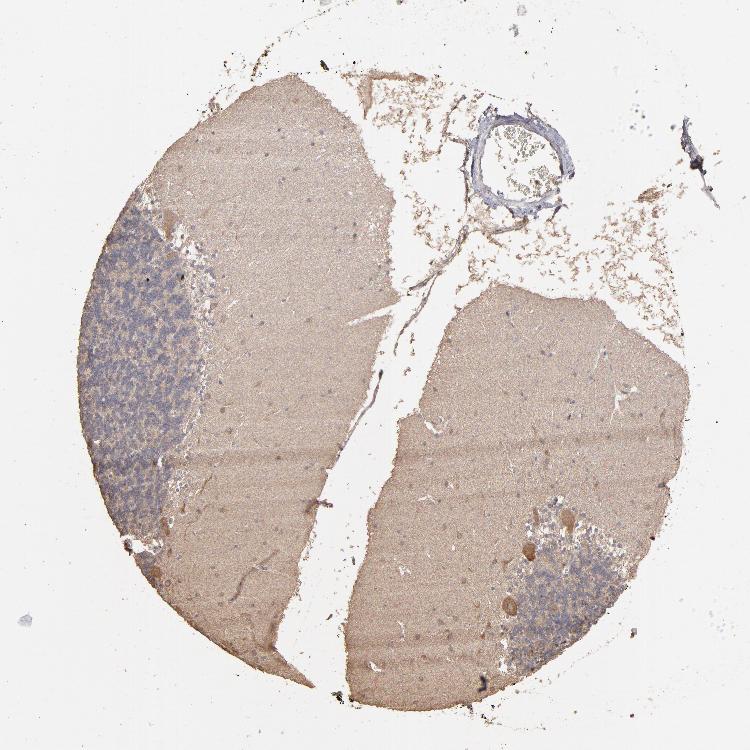

CEREBELLUM - Antibody stainingi

Antibody staining in the annotated cell types in the current human tissue is reported as not detected, low, medium, or high, based on conventional immunohistochemistry profiling in selected tissues. This score is based on the combination of the staining intensity and fraction of stained cells.

Each image is clickable and will lead to virtual microscopy that enables deeper exploration of all samples and also displays staining intensity scores, fraction scores and subcellular localization as well as patient and tissue information for each sample.

Antibody HPA001939Antibody CAB002788

Purkinje cells MediumNot detected

Cells in granular layer Not detectedNot detected

Cells in molecular layer MediumNot detected